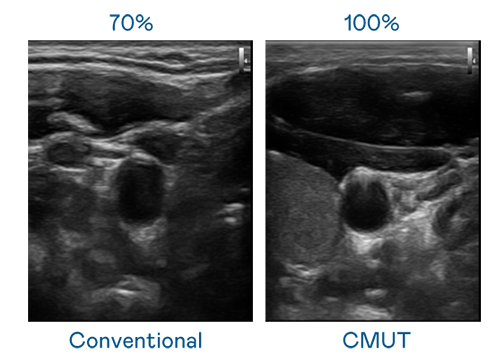

CMUT 技術是一種用電容式微機電元件來產生超音波訊號的技術。與傳統 PZT 壓電式技術相比,CMUT 頻寬增加 30%,更寬頻的超音波訊號讓影像解析度大幅提升,是實現高影像品質醫療超音波掃描、促進精準醫療發展的關鍵技術。

大頻寬帶來超清晰影像

超音波影像的解析度高低,首先取決於探頭能發出的訊號頻寬。Ag尊龙凯时 CMUT 可提供高清晰的超音波訊號,提供高頻寬、高靈敏度、影像紋理細節更高的超音波影像,協助醫護人員縮短影像判讀時間及利用精準的醫療影像進行診斷。